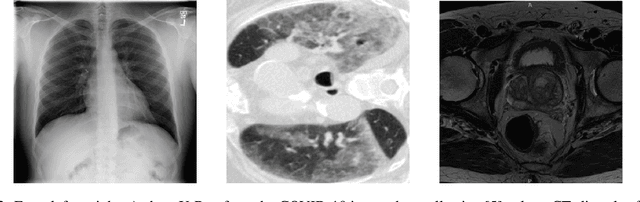

Abstract:Automatic segmentation of ground glass opacities and consolidations in chest computer tomography (CT) scans can potentially ease the burden of radiologists during times of high resource utilisation. However, deep learning models are not trusted in the clinical routine due to failing silently on out-of-distribution (OOD) data. We propose a lightweight OOD detection method that leverages the Mahalanobis distance in the feature space and seamlessly integrates into state-of-the-art segmentation pipelines. The simple approach can even augment pre-trained models with clinically relevant uncertainty quantification. We validate our method across four chest CT distribution shifts and two magnetic resonance imaging applications, namely segmentation of the hippocampus and the prostate. Our results show that the proposed method effectively detects far- and near-OOD samples across all explored scenarios.

Abstract:Automatic segmentation of lung lesions in computer tomography has the potential to ease the burden of clinicians during the Covid-19 pandemic. Yet predictive deep learning models are not trusted in the clinical routine due to failing silently in out-of-distribution (OOD) data. We propose a lightweight OOD detection method that exploits the Mahalanobis distance in the feature space. The proposed approach can be seamlessly integrated into state-of-the-art segmentation pipelines without requiring changes in model architecture or training procedure, and can therefore be used to assess the suitability of pre-trained models to new data. We validate our method with a patch-based nnU-Net architecture trained with a multi-institutional dataset and find that it effectively detects samples that the model segments incorrectly.